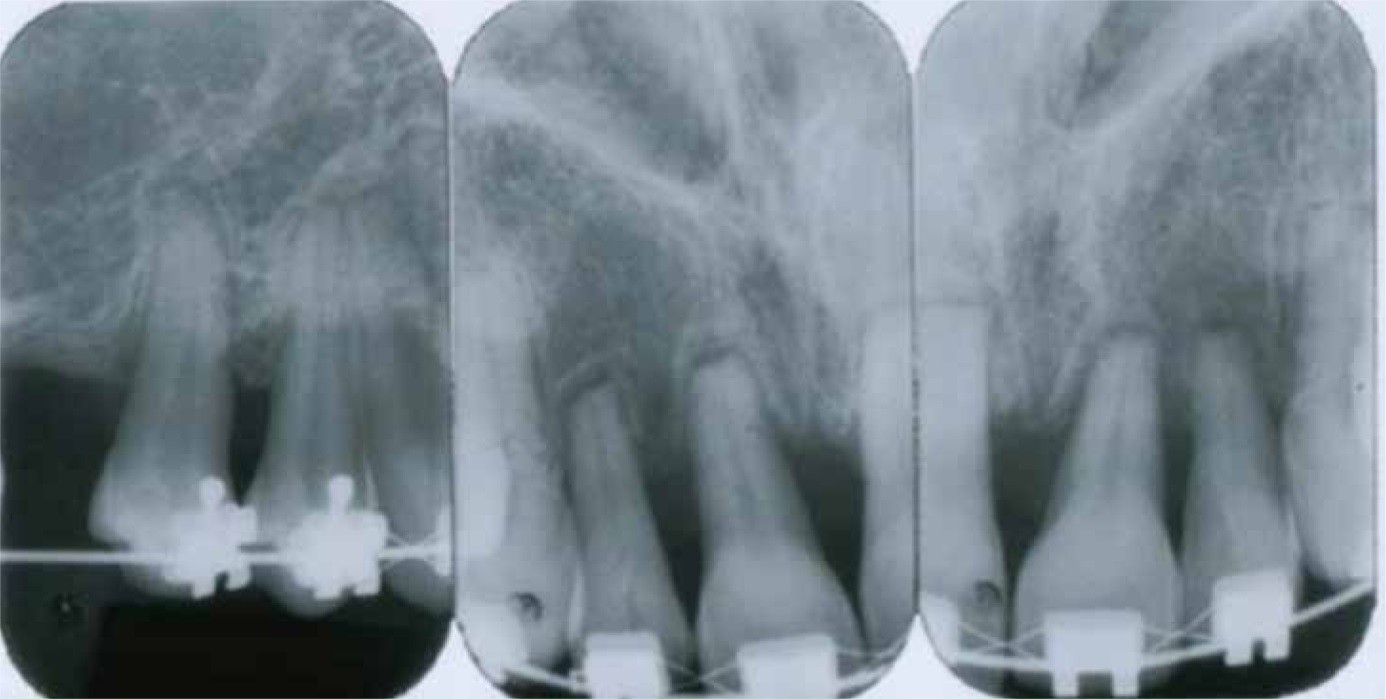

Lokalize Şiddetli Rezorpsiyon: Şiddetli generalize rezorpsiyonun aksine şiddetli lokalize rezorpsiyon bir çok durumda ortodontik tedavi nedeniyle oluşmaktadır. Uzun yıllardır ortodontik tedavi sırasında aşırı kuvvetlerin özellikle ağır devalı kuvvetler kullanıldığında kök rezorpsiyonu riskini arttırdığı bilinmektedir. Ortodontik tedavinin uzun sürmesi de kök rezorpsiyonu riskini arttırır. Şiddetli rezorpsiyon riski maksiller keserler için çok daha fazladır (%3’ü etkilenmiş, diğer dişlerde %1’den az). Kaley ve Phillips tedavi sırasında maksiller keserlerin kökleri lingual kortikal plate’e yaslanırsa şiddetli rezorpsiyon riskinin 20 kat arttığını belirtmiştir. Bimaksiller keserlere tork verildiğinde (Class II tedavisi) veya eğildiğinde (Class III tedavisi) bunun iskeletsel problemlerin kamuflaj tedavisinde oluşma ihtimali yüksektir. Maksiller keserle lingulae tipping yaptığında kökleri fasiyal kortikal plate’e temas eder veya alt molarların bukkal kök torku ankrajı arttırma amaçlı kullanılıyorsa kortikal plate’lere temaslar lokalize kök rezorpsiyonlarının diğer paternlerini açıklayabilir.